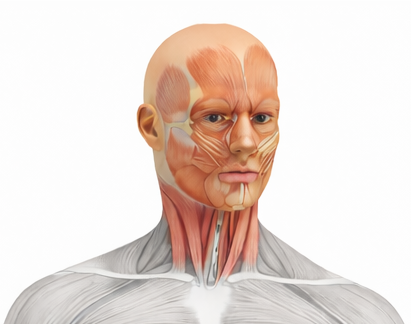

Head, Neck and Face

Learn Gross Anatomy of Head, Neck and Face including functional aspects, joints, nerves, vessels, and its clinical aspects.